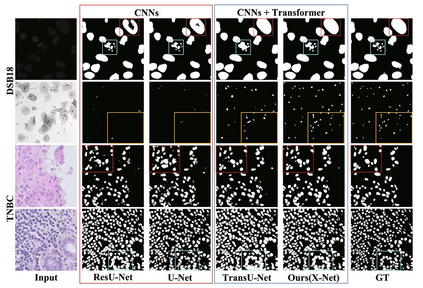

Transformer, the latest technological advance of deep learning, has gained prevalence in natural language processing or computer vision. Since medical imaging bear some resemblance to computer vision, it is natural to inquire about the status quo of Transformers in medical imaging and ask the question: can the Transformer models transform medical imaging? In this paper, we attempt to make a response to the inquiry. After a brief introduction of the fundamentals of Transformers, especially in comparison with convolutional neural networks (CNNs), and highlighting key defining properties that characterize the Transformers, we offer a comprehensive review of the state-of-the-art Transformer-based approaches for medical imaging and exhibit current research progresses made in the areas of medical image segmentation, recognition, detection, registration, reconstruction, enhancement, etc. In particular, what distinguishes our review lies in its organization based on the Transformer's key defining properties, which are mostly derived from comparing the Transformer and CNN, and its type of architecture, which specifies the manner in which the Transformer and CNN are combined, all helping the readers to best understand the rationale behind the reviewed approaches. We conclude with discussions of future perspectives.